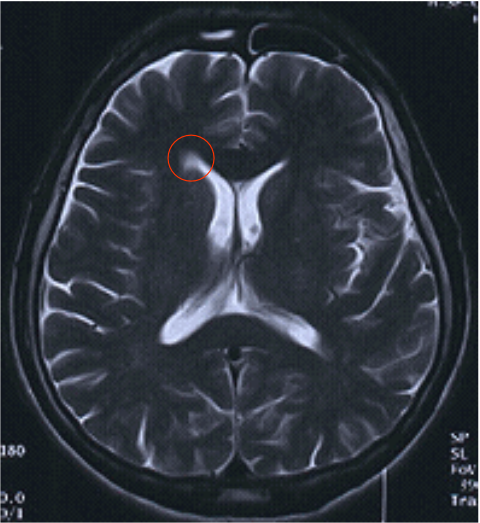

Comparaison T2 et T2 FLAIR B